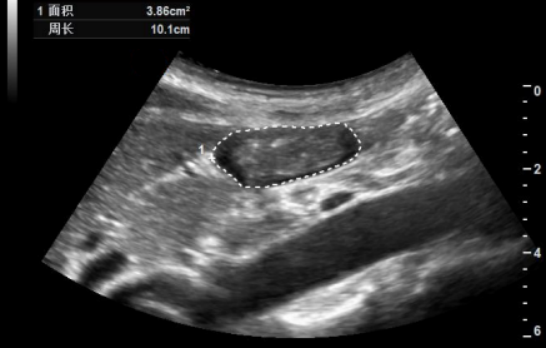

(2)描记法:描迹胃窦1周,获得胃窦CSA(cm210。

图片

10  描记法(图中虚线1为描记法)